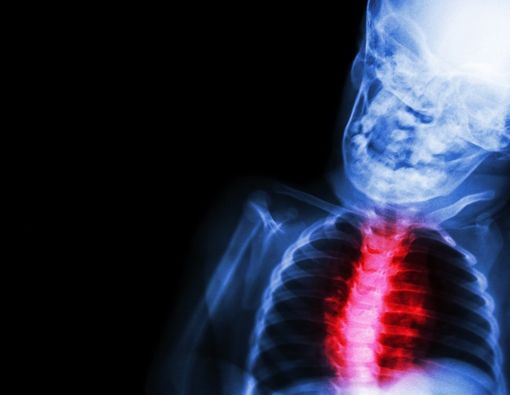

Itu dia beberapa faktor penyebab penyakit jantung bawaan pada janin. Penting bagi ibu hamil untuk selalu menjaga kesehatan dan menjalani pola hidup yang sehat demi kesehatan calon buah hati.